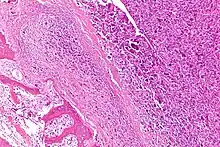

| Intermediate-magnification micrograph of an osteosarcoma (center and right of image) adjacent to non-malignant bone (left-bottom of image): The top-right of the image has poorly differentiated tumor. Osteoid with a high density of malignant cells is seen between the non-malignant bone and poorly differentiated tumor (H&E stain). | |

Microscopically: The characteristic feature of osteosarcoma is presence of osteoid (bone formation) within the tumor. Tumor cells are very pleomorphic (anaplastic), some are giant, numerous atypical mitoses. These cells produce osteoid describing irregular trabeculae (amorphous, eosinophilic/pink) with or without central calcification (hematoxylinophilic/blue, granular)—tumor bone. Tumor cells are included in the osteoid matrix. Depending on the features of the tumor cells present (whether they resemble bone cells, cartilage cells, or fibroblast cells), the tumor can be subclassified. Osteosarcomas may exhibit multinucleated osteoclast-like giant cells.[22]